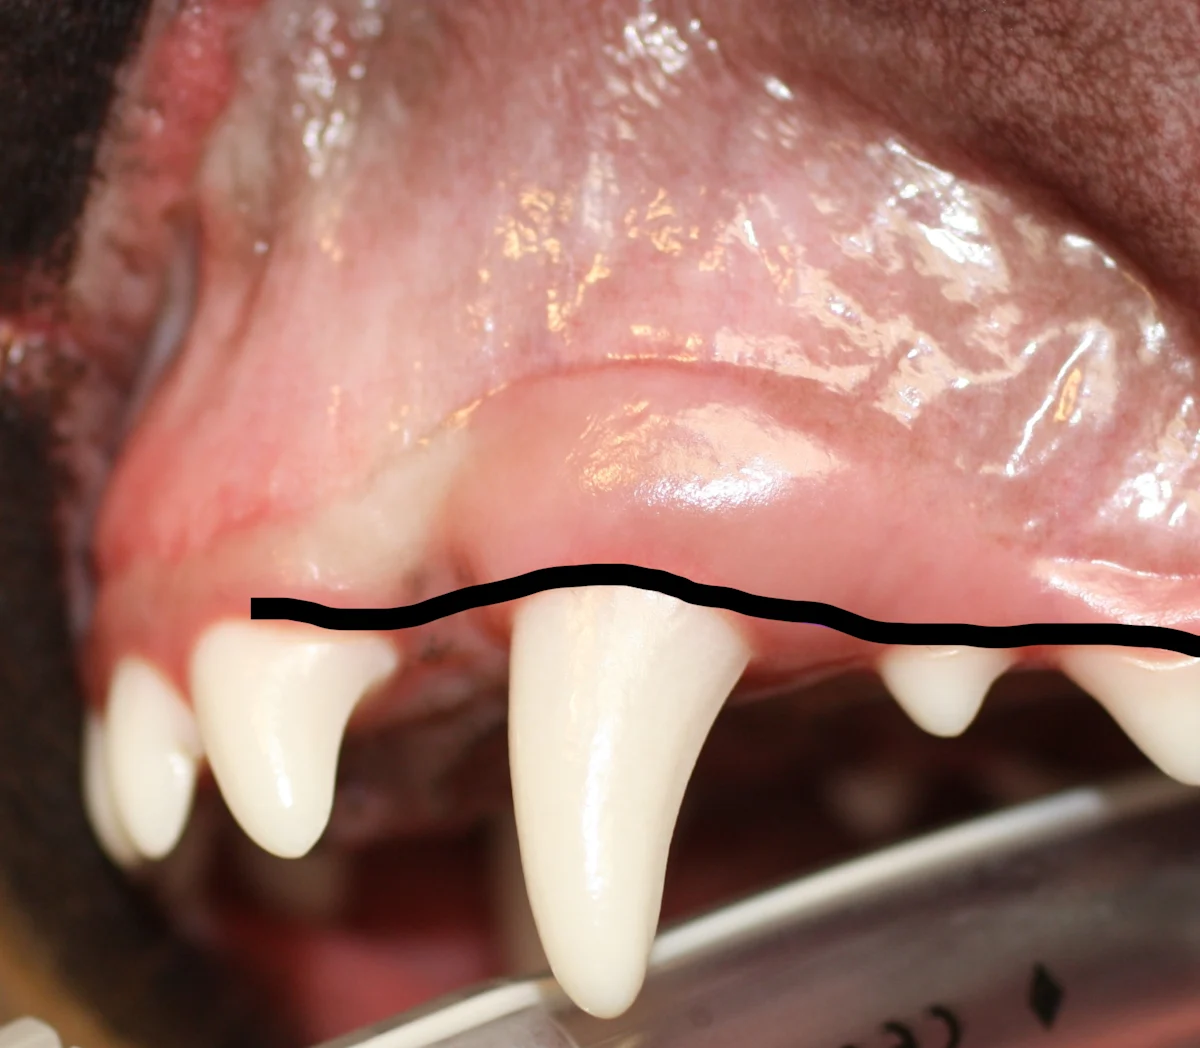

Envelope Flap

An envelope flap is created by making an incision at the ventral alveolar border (line). This type of flap may be preferred because vertical releasing incisions can contribute to complications (eg, dehiscence).